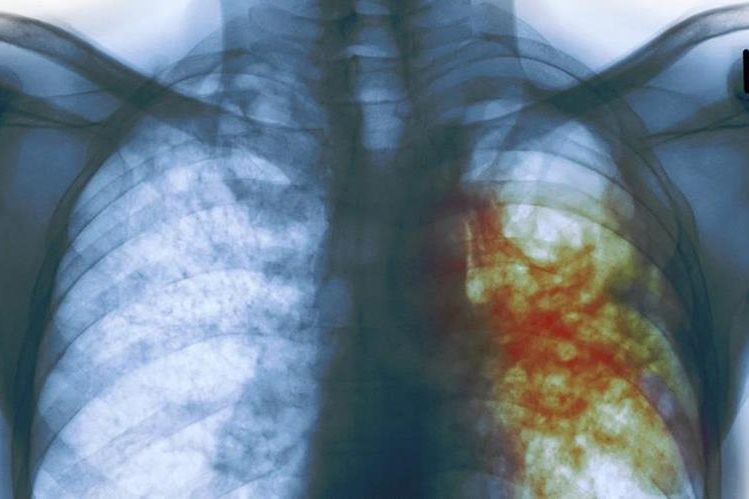

Radiografía de una persona con tuberculosis. (Foto Prensa Libre: Hemeroteca PL)

La bacteria Mycobacterium tuberculosis, es la causante de la enfermedad, la cual afecta principalmente a los pulmones. Aunque la tuberculosis es una enfermedad riesgosa, también es curable y sobre todo se puede prevenir.

La bacteria Mycobacterium tuberculosis, es la causante de la enfermedad, la cual afecta principalmente a los pulmones. (Foto Prensa Libre: Hemeroteca PL)